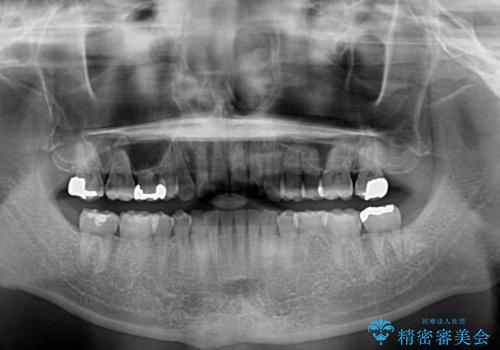

右上と左下は永久歯が欠如しており、大きさの大きく異なる乳歯が残存していたため、奥歯の咬み合わせを構築するために苦労しました。